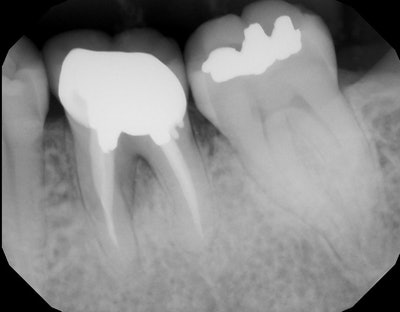

The patient in this case presented with a nonrestorable, root canal-treated mandibular molar tooth (figures 1-3). After patient consultation, it was decided that the tooth would be extracted and grafted in preparation for a dental implant.

Since the roots were divergent and it was a mandibular molar tooth where the bone is more dense, the treatment plan included the following:

- The crown would be removed.

- The tooth would then be sectioned and extracted as individual roots.

- The site would then be grafted with a simple technique in preparation for a future dental implant.